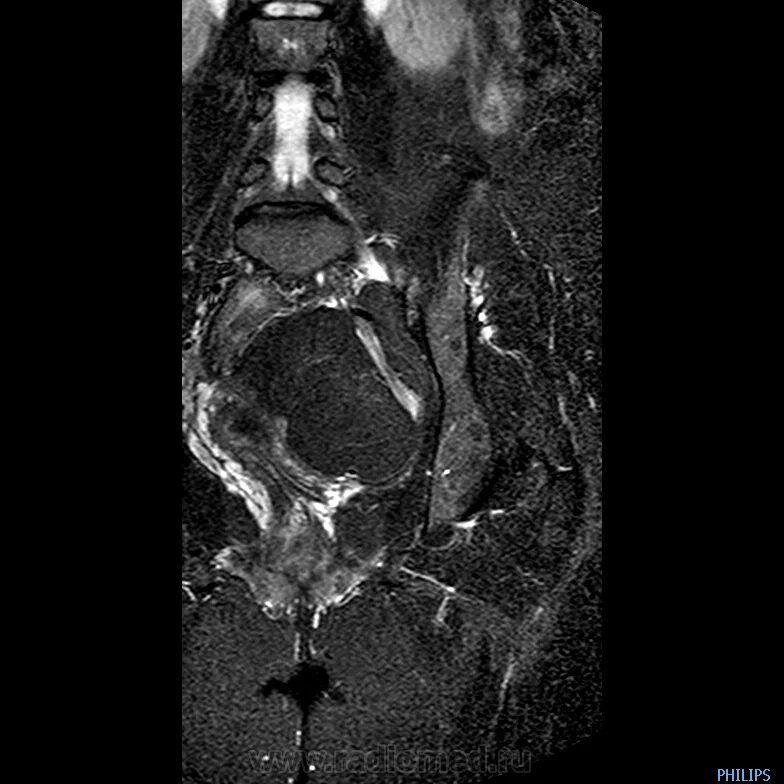

Солидное образование в малом тазу